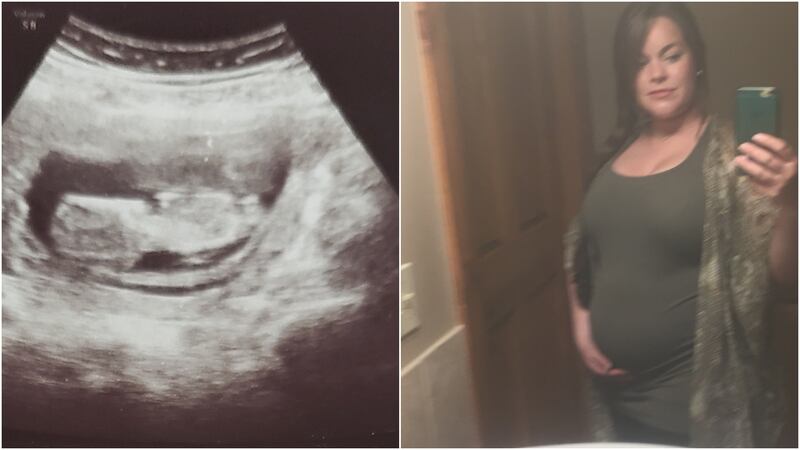

Chantal Reh never got to know her daughter Christie, who had been diagnosed in the womb with Turner’s Syndrome, a rare chromosomal disorder, and was stillborn.

Chantal Reh never got to know her daughter, Christie.

Reh and her partner took their first and last photos with Christie back in 2018, and the hospital released the body to Staci Kent—who promptly went dark.